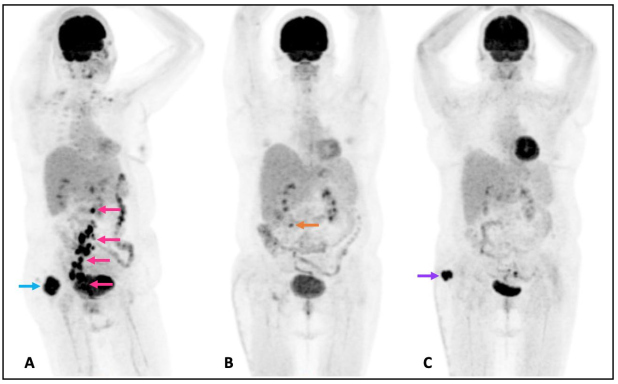

Mujer de 49 años con antecedente de leucemia de células pilosas (tricoleucemia) de riesgo bajo, en remisión completa. En septiembre 2020 presentó aumento de volumen en región supero-interna del glúteo derecho; ante la sospecha de una infección de tejidos blandos recibió antibióticos, sin mejoría. El mismo mes fue valorada en nuestra institución por la presencia de una neoformación cutánea dolorosa en glúteo derecho. Se realizó ecografía de la lesión dérmica (fig.1) y una tomografía de abdomen y pelvis en fase venosa, donde se observó una lesión sólida de 45 x 24 x 41 mm, con márgenes bien definidos y lobulados. Además se detectaron adenopatías ilíacas comunes, en cadena ilíaca interna derecha y en región inguinal homolateral, de entre 15 y 51 mm. Referida la paciente al servicio de Dermatología, la lesión fue descrita como una neoformación de aspecto nodular, cupuliforme, de 4 x 5 cm de diámetro, superficie lisa y violácea, sólida, a la dermatoscopía con patrón reticular y áreas rosas y blancas, sin estructura (fig. 2). Posteriormente se realizó biopsia por huso de la lesión glútea, con reporte de patología de carcinoma invasor de células de Merkel con invasión a dermis profunda (CK-, CK20+, Cromogranina +, Sinaptofisina -, Ki67 80%, CD56+, CD117+); además se tomó una biopsia excisional del conglomerado ganglionar inguinal, que confirmó la presencia de metástasis. Como parte de su estadiaje, en enero de 2021 se realizó un estudio PET/CT con 18F-FDG que documentó incremento focal del metabolismo en la lesión, así como adenopatías hipermetabólicas cervicales, retroperitoneales, ilíacas bilaterales e inguinales derechas. Debido a un sangrado no controlado del tumor, se procedió a la resección de la lesión glútea y colgajo de muslo posterior sin complicaciones, reportando márgenes quirúrgicos negativos. Al tratarse de una enfermedad metastásica, se administró quimioterapia a base de etopósido y cisplatino, en 5 ciclos desde marzo a junio y se realizó nuevo PET/CT con 18F-FDG para evaluar respuesta a tratamiento. Por presentar oligo-progresión ganglionar (adenopatía pericecal hipermetabólica), recibió radioterapia corporal estereotáctica (SBRT) 45Gy en 6 sesiones desde junio a julio de 2021. En agosto se realizó un nuevo PET/CT donde se observó desaparición de la adenopatía antes mencionada y una nueva lesión nodular de bordes lobulados en región glútea derecha de 36 x 32 mm con SUV máximo de 15,6. La fig. 4 muestra el MIP de los 3 estudios PET/CT: inicial, post-resección + quimioterapia y post-radioterapia. La paciente continuó su tratamiento experimentando respuesta completa aunque más tarde se comprobó recaída local y ganglionar, todo lo cual fue documentado mediante PET/CT, no incluído en esta publicación.